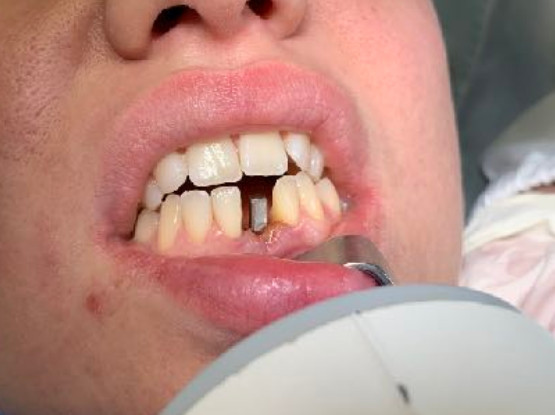

| Saldatura : No | Zona dentale: incisivo inferiore 31 |

| Situazione estrattiva: Impianto postestrattivo immediato a carico immediato. | Densità secondo Misch: D2 |